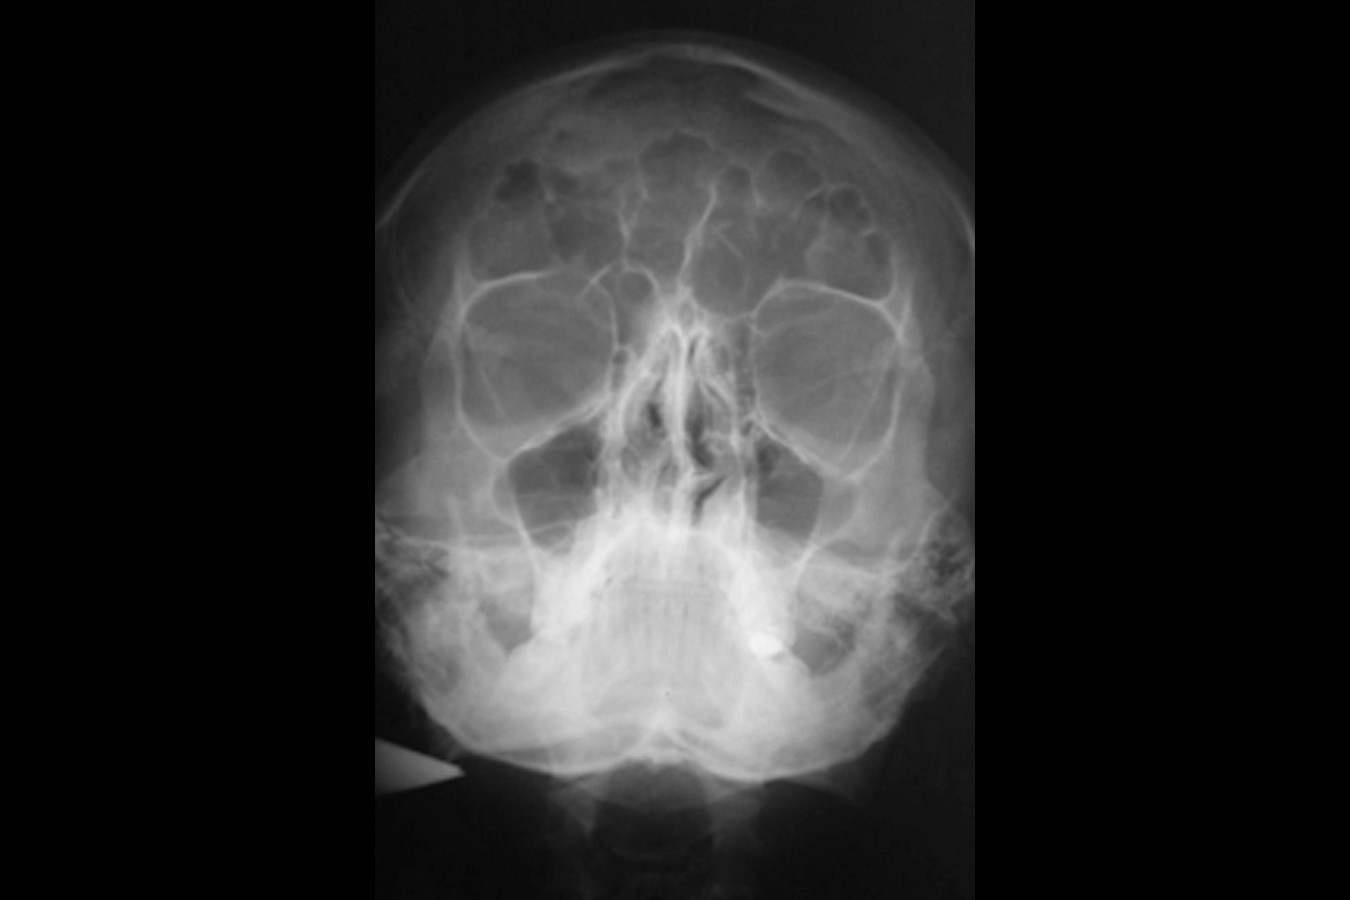

Przed podjęciem leczenia należy określić stopień zaniku kości szczęk oraz żuchwy. W tym celu przeprowadza się badanie kliniczne oraz odpowiednią diagnostykę obrazową pacjenta. Uwzględnia ona zdjęcie panoramiczne OPG jako podstawę dwuwymiarowego obrazowania podłoża kostnego oraz możliwe jest badanie tomograficzne CT lub bardziej precyzyjna tomografia stożkowa CBCT. Opcjonalnie wykorzystywana diagnostycznie tomografia pozwala na bardziej wnikliwą ocenę stopnia zaniku kości w trójwymiarowym, przestrzennym obrazie.

Zatoki szczękowe to symetrycznie umieszczone w kościach szczęk przestrzenie powietrzne, posiadające komunikację z jamą nosa. Średnio pojemność zatok wynosi 24 cm3, a ściany wyścielone są błoną śluzową (membrana Schneidera). Dno zatoki szczękowej stanowi wyrostek zębodołowy, w którym umieszczone są zęby, często zlokalizowane tuż pod cienką wyściółką zatoki. Statystycznie najwęższy obszar kostny w tej strefie zlokalizowany jest na wysokości zębodołów pierwszego i drugiego zęba trzonowego.